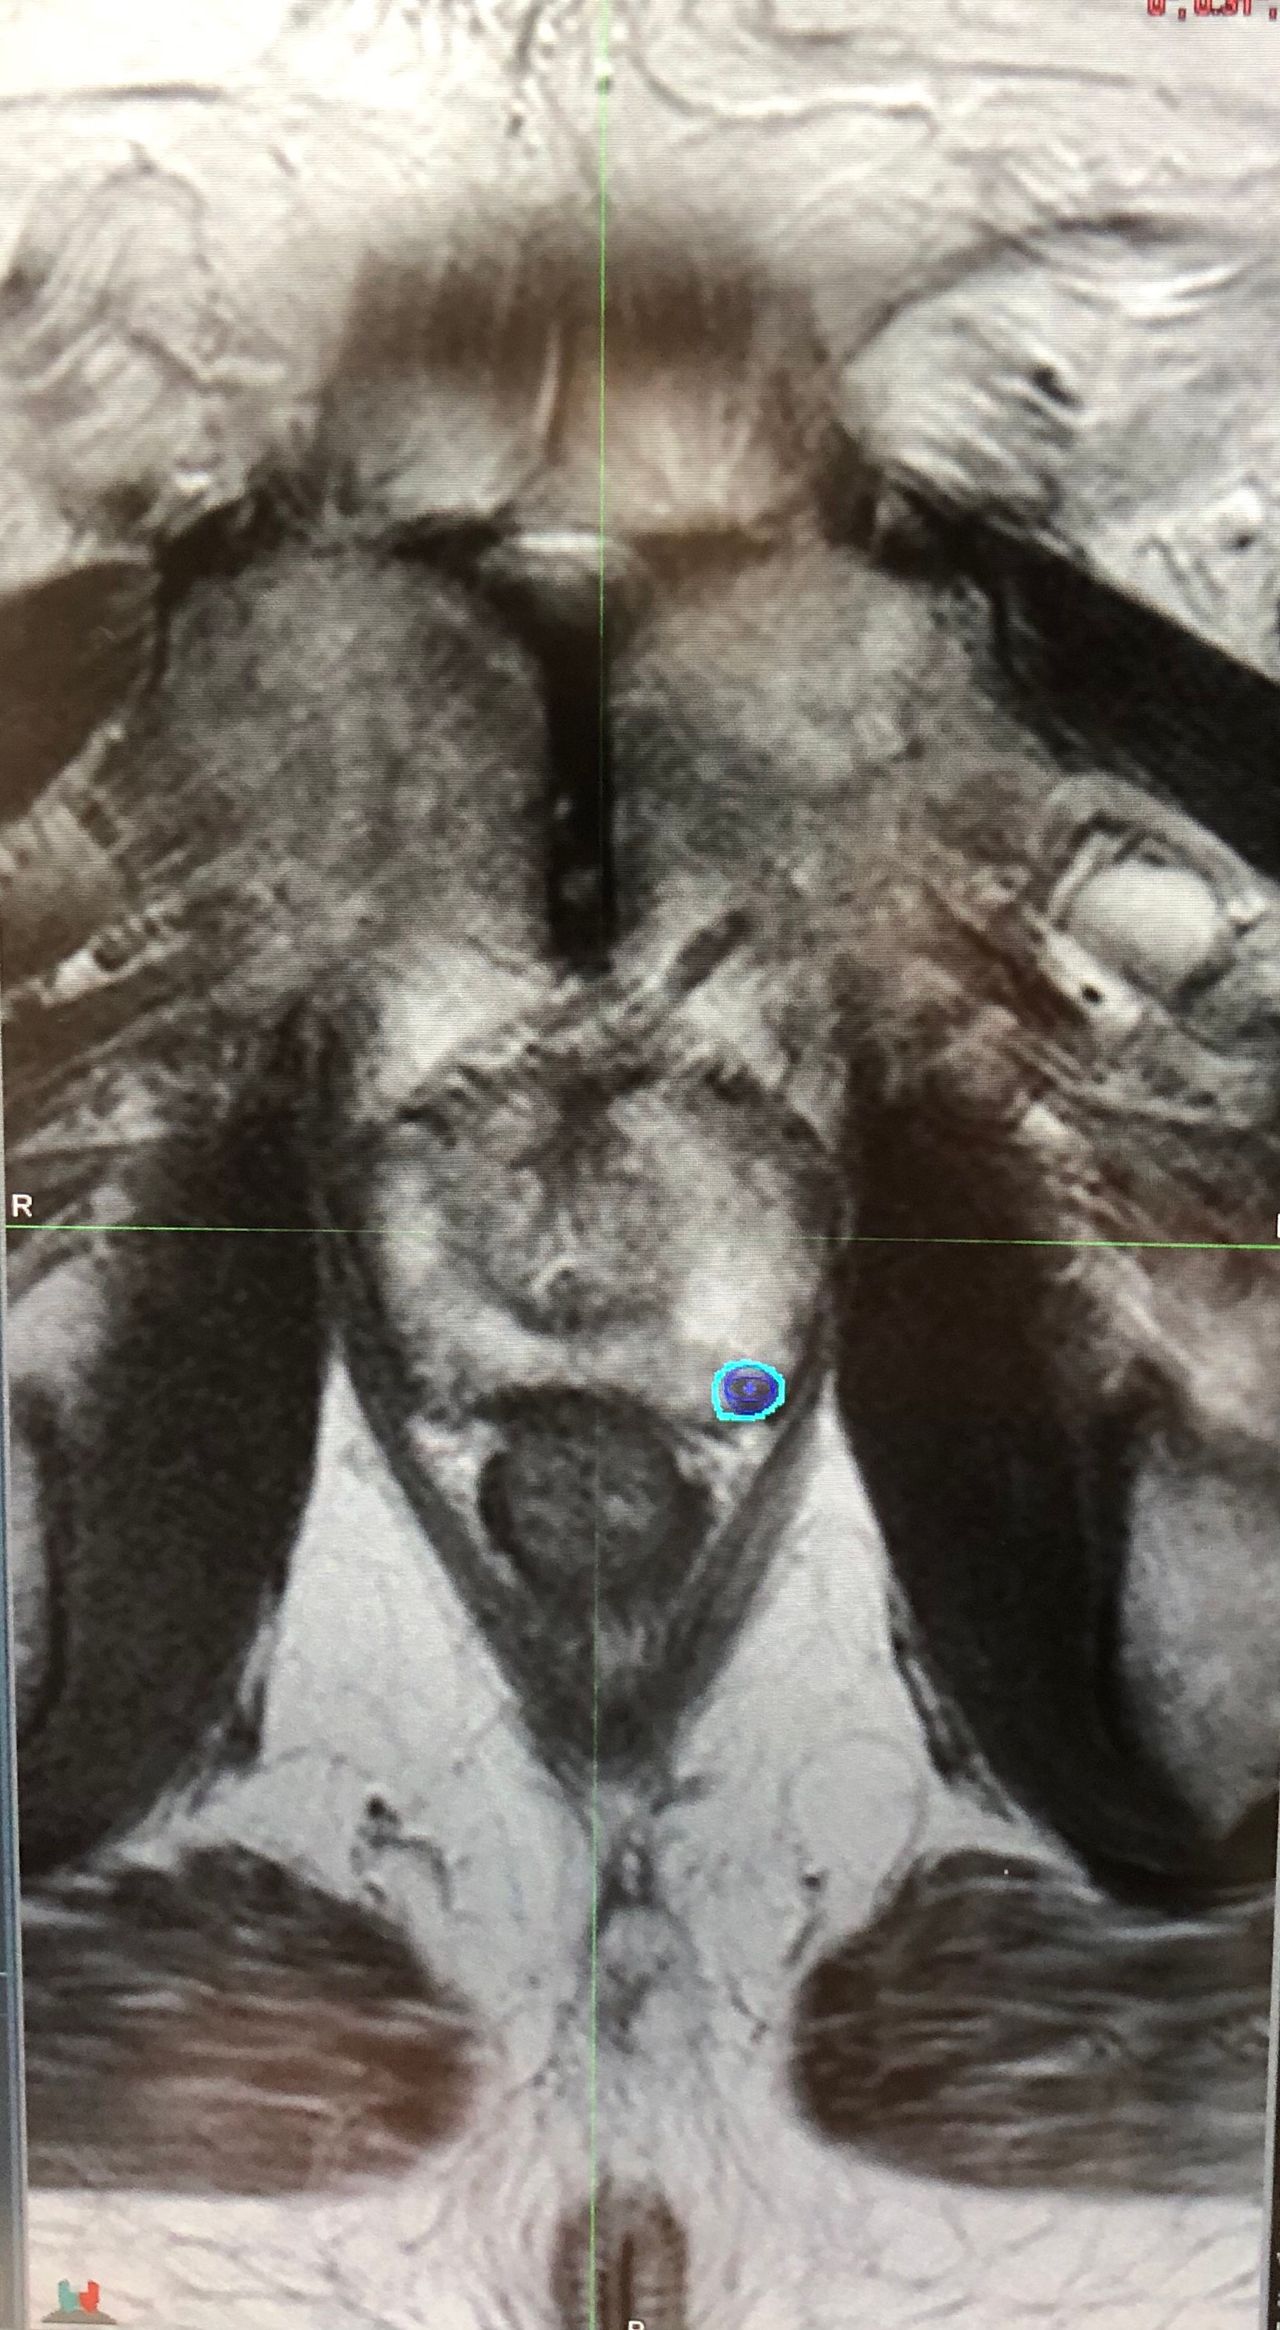

Rozprawa doktorska pt:" ANALIZA PRZYDATNOŚCI WYSOKOPOLOWEJ TOMOGRAFII MR W OCENIE ZAAWANSOWANIA RAKA GRUCZOŁU KROKOWEGO Z UWZGLĘDNIENIEM STOPNIA ZRÓŻNICOWANIA PATOMORFOLOGICZNEGO WEDŁUG KLASYFIKACJI GLEASONA."

- biopsja gruczołu krokowego z oceną MRI w skali PI RADS

Dzień dobry, uprzejmie proszę o podpowiedź co robić dalej. Mam 61 lat. PSA 7,98 indeks 13%.

Poniżej wynik rezonansu magnetycznego.

Prostata o wym. 38x44x61 mm (APxSDxCC), z cechami znacznego rozrostu części centralnej, wpukla się w obręb

pęcherza moczowego na odległość około 13 mm.

Na pograniczu piętra wierzchołkowego i środkowego uwidoczniono w strefie obwodowej dwie linijno-klinowate

zmiany w części bocznej oraz w części tylnej o obniżonej intensywności sygnału. Jedna z nich (w części tylnej)

wykazuje cechy wzmocnienia pokontrastowego oraz niewielkiego ograniczenia dyfuzji - wskazana dalsza obserwacja

zmiany lub biopsja. PIRADS 3/4. Druga zmiana (w części bocznej) bez ewidentnych cech wzmocnienia

pokontrastowego oraz ograniczenia dyfuzji - prawdopodobnie zmiana bliznowata do dalszej obserwacji. PIRADS 3.

Strefa przejściowa ze względu na liczne gruczolaki trudna do oceny. Na pograniczu piętra środkowego i podstawnego

w tylno-bocznej części strefy przejściowej płata prawego uwidoczniono obszar o obniżonej intensywności sygnału o

wymiarach orientacyjnych 13x5 mm, która koreluje z obniżeniem sygnału na mapach ADC, jednak nie wykazuje cech

patologicznego wzmocnienia pokontrastowego - prawdopodobnie zmiana bliznowata - do dalszej obserwacji ze

względu na wysoki wynik PSA. PIRADS 3.

Innych podejrzanych zmian ogniskowych w obrębie prostaty w badaniu nie uwidoczniono.

Podejrzanych radiologicznie węzłów chłonnych miednicy mniejszej w badaniu nie uwidoczniono.

Pęcherzyki nasienne bez cech patologii.

Pęcherz moczowy miernie wypełniony o dyskretnie nierównych obrysach.

Uwidocznione struktury kostne bez cech patologii.

Innych zmian nie stwierdza się.

Wnioski:

Podejrzana zmiana ogniskowa w obrębie strefy obwodowej płata lewego. Wskazana dalsza obserwacja zmiany, w razie dalszej

tendencji wzrostowej PSA wskazana biopsja. Poza tym dwie zmiany do dalszej obserwacji. Wszystkie zmiany oznaczone na

schemacie obrazowym w załączeniu.

PIRADS 3/4 (w zależności od kolejnego wyniku PSA).

Dzień Dobry Mr to tylko składowa diagnostyki

Proszę do wartość PSA

CZY BYŁO BADANIE PER RECTUM

zapraszam na konsultacje postaram się wyjaśnić